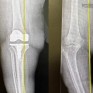

مستشفى الحبيب بالخبر يُجري عملية زراعة مفصل معقدة لإعادة قدرة المشي لثمانينية

مستشفى الحبيب بالخبر يستبدل مفصلي الركبة والورك وعظمة الفخذ ويعيد “الحركة” لـ”ستينية”

قفزة نوعية في جراحات العظام.. الدمام الطبي ينجح في استبدال الركبة باستخدام الروبوت

بعد 5 محاولات جراحية لم تنجح.. مستشفى الحبيب بالخبر يُمكّن سبعينية من المشي مجددًا

نجاح أول عملية استبدال ركبة بالروبوت الجراحي في مستشفى الدكتور سليمان الحبيب بالخبر